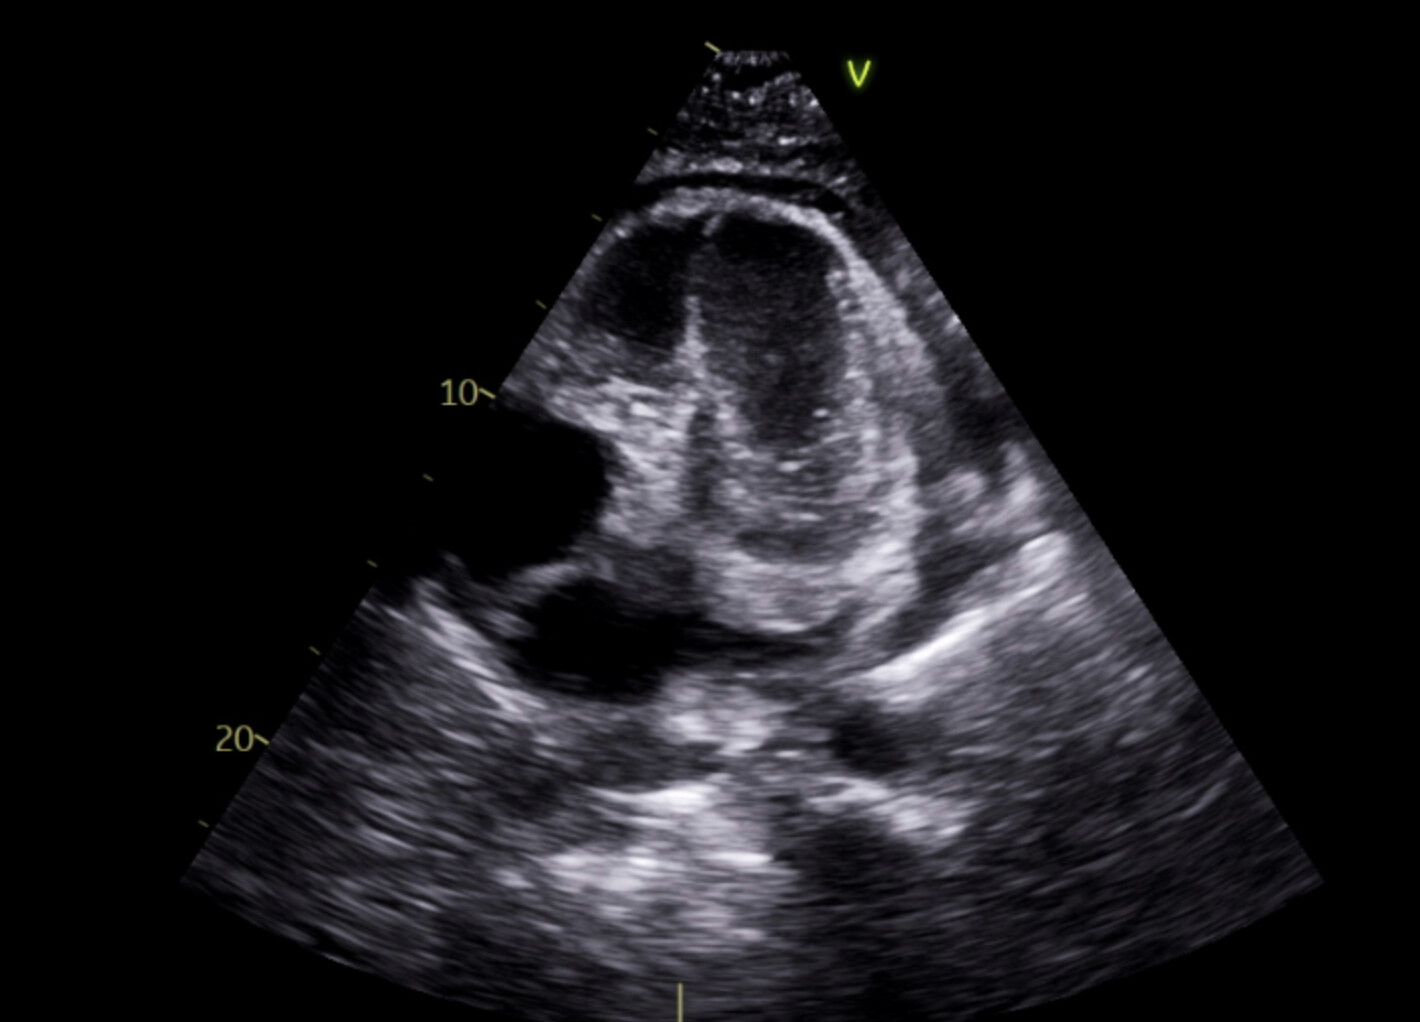

Abstract Body (Do not enter title and authors here): A 40-year-old male with past medical history of Methicillin-resistant staphylococcus aureus endocarditis treated with open valve replacement of tricuspid valve and resection of aortic valve vegetation, history of deep vein thrombosis with Inferior Vena Cava filter placement, history of IV drug use, acute cholecystitis requiring percutaneous cholecystostomy tube placement, type 2 diabetes mellitus on chronic insulin therapy, hypertension, hyperlipidemia, degenerative spine disease who presents to an urgent care facility due to hallucinations. At the urgent care facility, imaging showed a pericardial effusion for which he was sent to our hospital. A CT chest without contrast on admission showed a large pericardial effusion, redemonstrated on transthoracic echocardiogram. Patient underwent subxiphoid pericardial window creation with pericardial drain placement with cardiothoracic surgery, draining a total of 2265ml of murky yellow fluid over 7 days. Pericardial fluid grew Candida Auris, for which the patient was treated with 10 days of intravenous micafungin initiated on admission day 6.